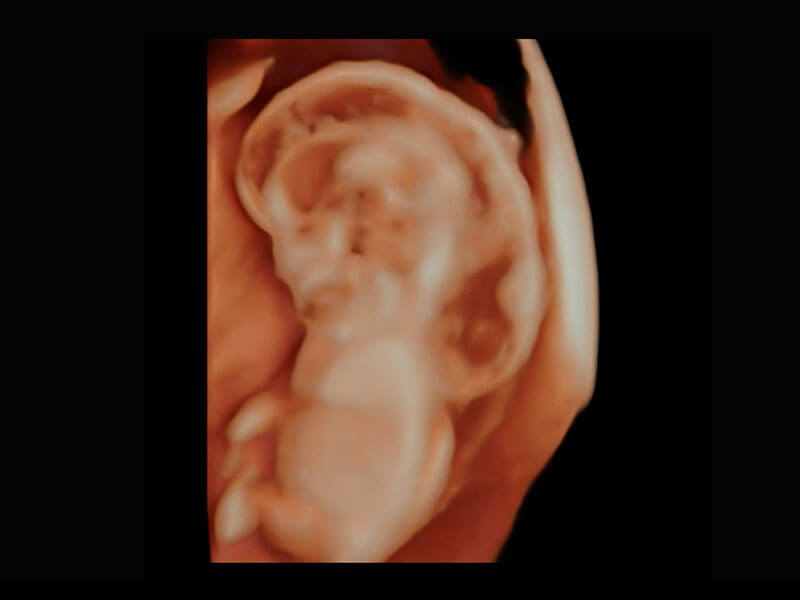

P60在胎兒早孕期超聲篩查中為您帶來(lái)優(yōu)異的圖像質(zhì)量。

高分辨率容積成像-早孕胎兒